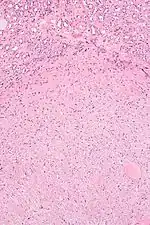

| Micrograph of a renal medullary fibroma (bottom of image). Renal tubules are seen at the top of the image. H&E stain. | |

They consist of bland spindle-shaped or stellate-shaped cells in a loose stroma. Renal tubules may be entrapped.